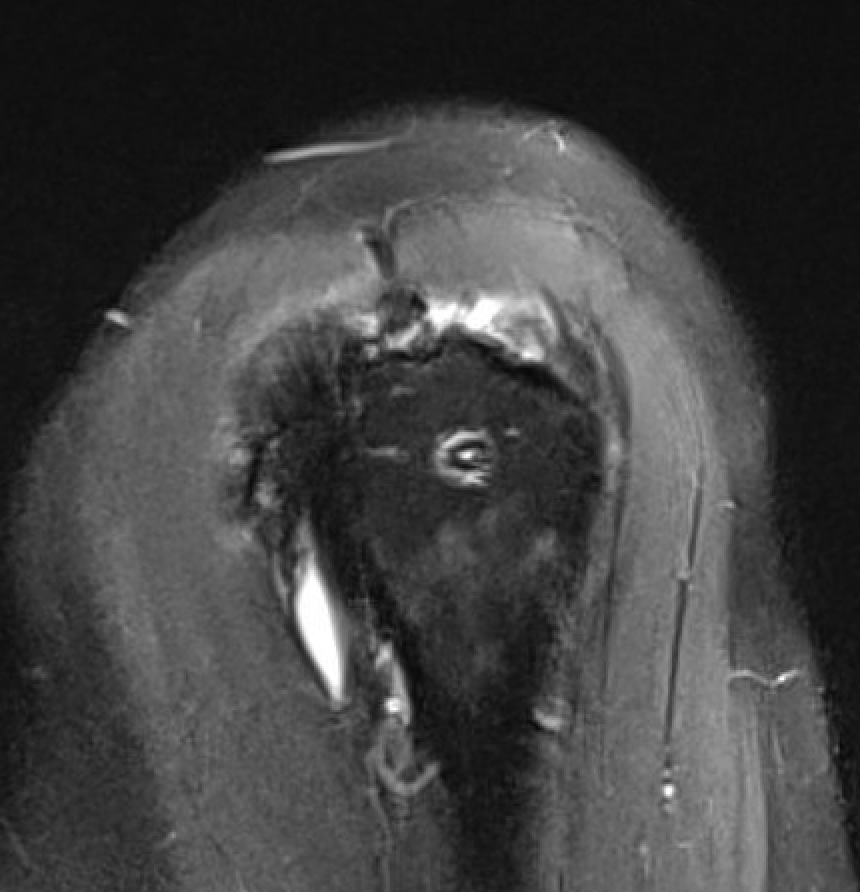

Retear

Increased risk with larger tear size and patient age

- 1000 arthroscopic RCR with ultrasound at 6 months

- retear in 27% of full thickness tears

- increased risk as tear size increased

- increased risk with older patients

- 1600 arthroscopic RCR

- retear rate 7% with cuff tears < 2 cm2

- retear rate 44% with tears > 8 cm2

Retear

Presentation

Pain / stiffness / weakness

Incidence

- 1600 arthroscopic RCR

- retear rate 7% with cuff tears < 2 cm2

- retear rate 44% with tears > 8 cm2